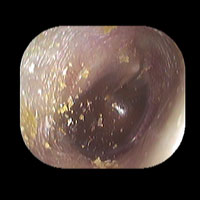

右急性中耳炎(中等症)

鼓膜がやや赤くなっています。鼓膜の奥に膿が透けて見えています。鼓膜の腫れはありません。抗生剤の内服で鼓膜切開を行わずに16日目で治りました。

7日目